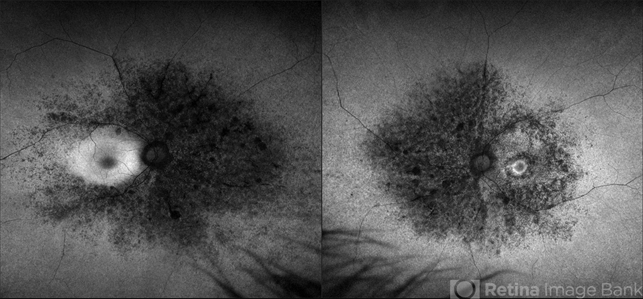

Optos California - Description

- Optomap RGB and AF of an 63-year-old man with secondary pigmentary degeneration of the retina. Patient's Spark genetic testing revealed heterozygous mutations of unknown significance in LRP5, COL18A1, CPLANE1, SLC24A1 and VCAN. Clinical findings most consistent with Wagner's Syndrome (VCAN mutation, autosomal dominant). Will continue follow up care every 6 months with dilated exam and repeat OCT and Optos imaging .